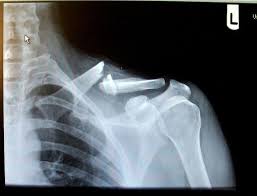

X Rays Of Broken Bones 20090323 Brokenclav Lance Armstrongs Broken Collarbone Broken Bone Medical Information Medical